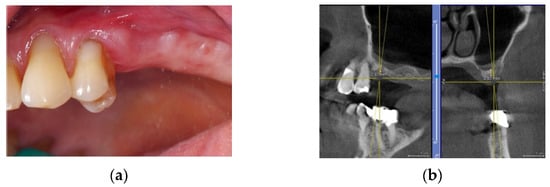

4 months after the surgery, the barrier was withdrawn and, behind it, growth of elastic and thick osteoid tissue was observed (Figure 16a,b). After further 4 months, a CBCT was performed, and the amount of regenerated bone was observed (Figure 17a–d).

Figure 16.

(a) Removal of titanium foil after 4 months; (b) osteoid tissue with hard but still elastic consistency covered by not-epithelized mucosa.

Figure 17.

(a) Initial 3D situation; (b) CBCT of the initial situation; (c) Final CBCT post 3D regeneration after 4 months; (d) X-ray of the situation post regeneration after 4 months.

The patient was prosthetically rehabilitated with additional implants positioned in 4.2 and 3.2 (post-extractive). In this case, we also noted how soft tissues surrounding the regenerated site were mature and stable (Figure 18).

Figure 18.

Prosthetic finalization of the case and mucose quality.